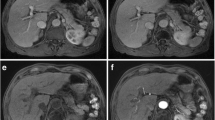

Image analyses of T1-weighted pre-contrast as well as dynamic post-contrast arterial phase and portal venous phase (PVP) were performed by on-site board-certified radiologists with experience in abdominal MR imaging of more than 6 years. Respiratory imaging artifacts were graded with a 4-point scoring system: G1 = no artifacts, G2 = mild artifacts, no effect on diagnostic quality, G3 = moderate artifacts, impeded diagnostic quality, G4 = severe artifacts, non-diagnostic. For further analyses, grades 3 and 4 were defined as substantial artifacts, grade 4 as severe artifact (Fig. 3). The readers were blinded regarding patients’ breath-hold failure and subjective dyspnea. All data collection was carried out using a standardized questionnaire. To standardize the grading of artifacts by the 8 radiologists, sample images for G1–G4 were placed on the questionnaire to let them grade the images by referring the sample side-by-side.